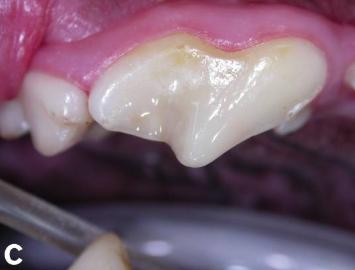

而到了第四、五阶段,则需要完全拔掉牙齿,并且在牙齿周围使用密封剂,以防止进一步的扩散。根据牙齿持续损坏的时间和面积,兽医会用精密仪器观察牙龈瓣内部,清除坏死组织并治疗,促进牙龈组织愈合。

蛀牙已得到完全修复